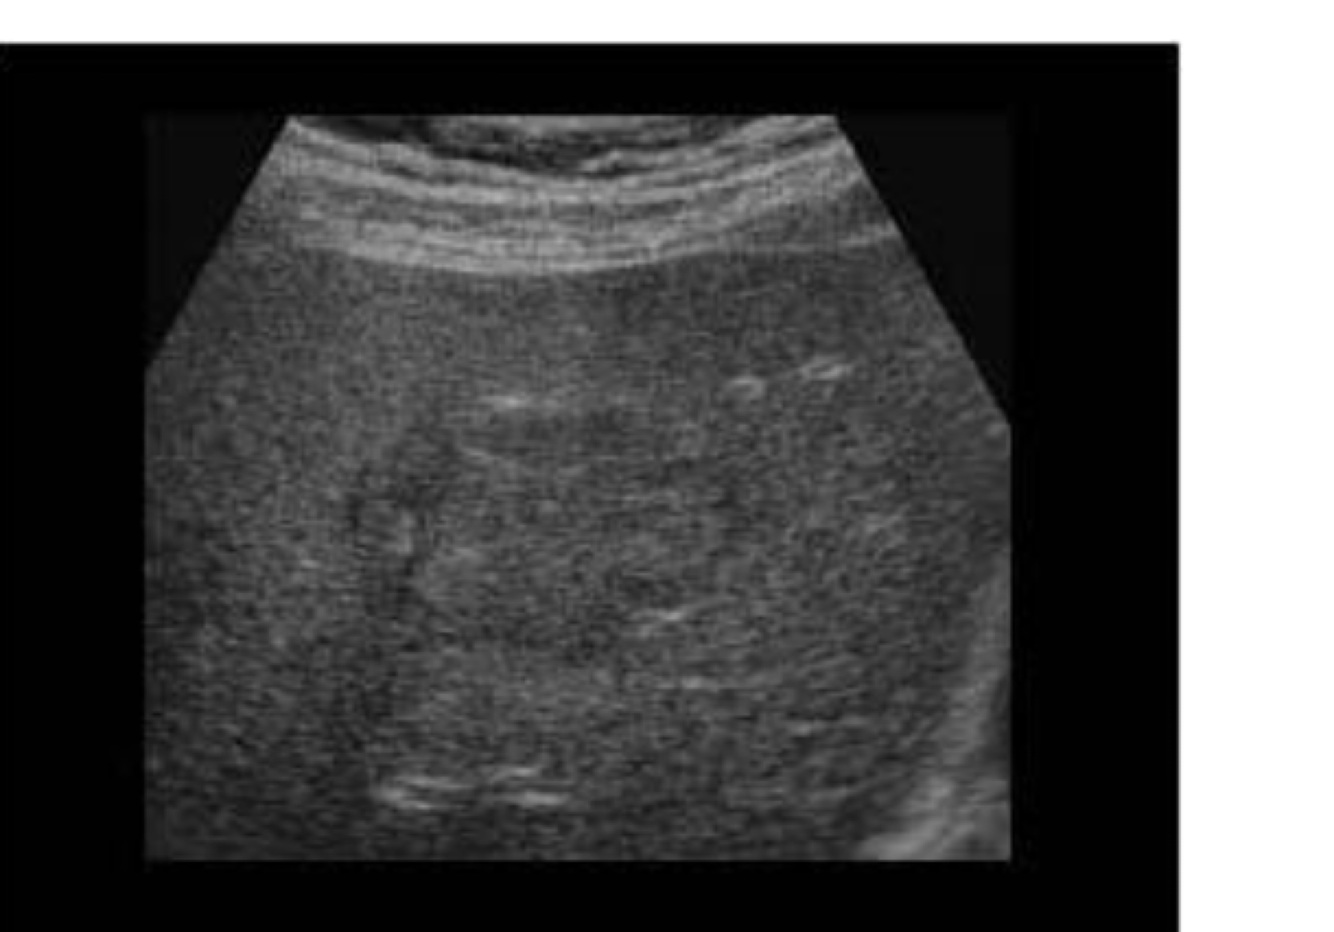

In terms of a diffuse disease what is evaluated?

Overall echogenicity and echotexture of an organ

In terms of diffuse disease what does echotexture changes mean?

Heterogeneous: irregular or patchy parenchyma